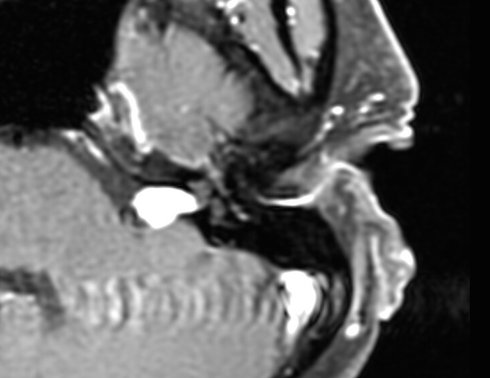

Dr. Fishman lead a team of surgeons from the NATO Military Hospital in Bydgoszcz Poland to perform the first hearing preservation acoustic neuroma removal by the novel “Retrolabyrinthine Approach”. The surgery was performed by doctors and nurses in the NATO regional hospital and the team was successful in completely removing the tumor and preserving both hearing and facial function in the young patient.